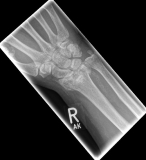

Handgelenk 1Often the inspection of the wrist already shows a suspected diagnosis. The accident mechanism must be clarified and after the physical examination, X-ray images of the wrist must be made in 2 levels.

In the classification of the distal radius fractures, the position of the fracture as well as a possible involvement of the articular surface are considered. Furthermore, the accident mechanism allows a classification of the fractures: the fall on the outstretched hand leads to a so-called extension fracture (Colles fracture), while the fall on the bent hand leads to a flexion fracture (Smith fracture).